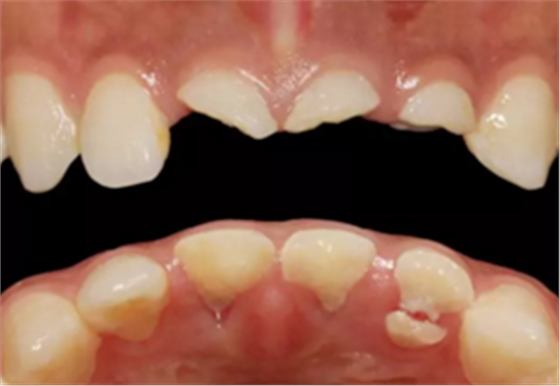

患者,女性,23岁,外伤导致上前牙折断3天。检查:中微笑 线;上颌右侧中切牙至左侧侧切牙残根,不松动,腭侧缺损达龈下5mm, 牙龈中等厚度,龈缘基本完好。CBCT显示:根长约11mm,牙根长轴与牙 槽突方向基本一致,唇侧骨板完好、厚度1.0mm,可用骨高度21mm。全身情况良好。

临床诊断:上颌右侧中切牙至左侧侧切牙冠根折。

图2 术前口内像